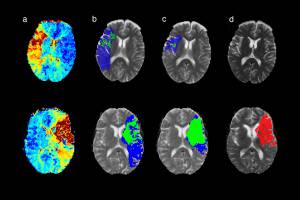

Die in Bern entwickelte Software FASTER kann innert Minuten erfassen, welche Hirnareale nach einem Schlaganfall langfristig geschädigt bleiben.